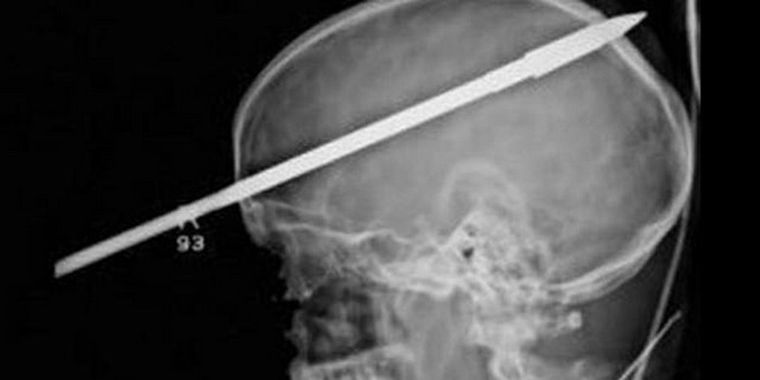

El joven fue trasladado inmediatamente al hospital Jackson de Miami donde llegó consciente y aparentemente tranquilo. Tuvieron que serrarle parte de la lanza para poder hacerle radiografías que muestran unas imágenes espectaculares del cerebro del joven.

Tres horas estuvieron operándolo para salvarle la vida y extraerle la punta que le entró a la altura del ojo derecho y atravesó su cerebro milagrosamente sin tocar vasos sanguíneos importantes.